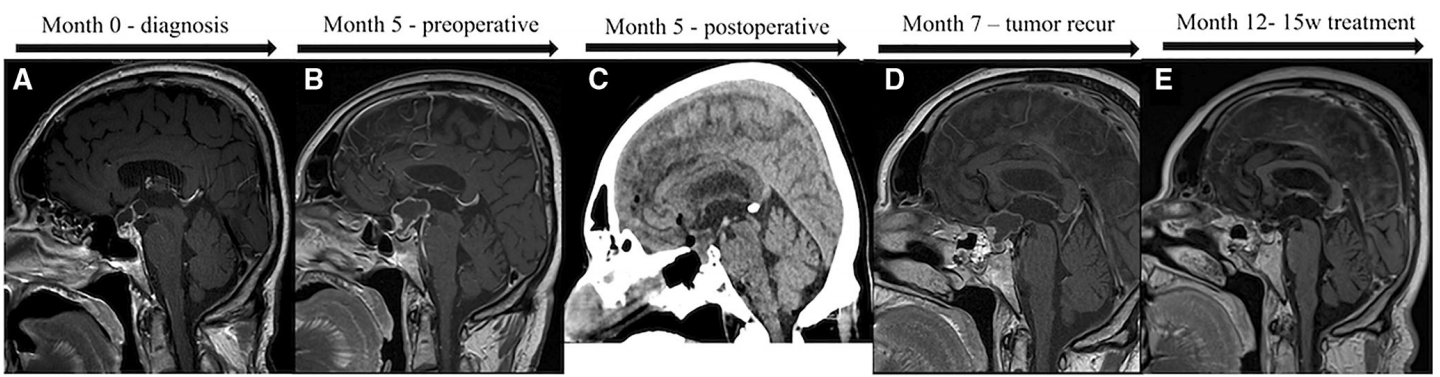

患者是一名65岁男性,因恶心和在3个月内体重骤降15公斤而入院。恶性肿瘤检查包括胸部和腹部的CT检查,没有任何病理表现,但血液检查显示垂体功能不全。脑CT和MRI显示鞍上肿块(3.1 cm3)(图1a),囊性成分抬高了视神经交叉,怀疑是颅咽管瘤。后来,患者也出现双侧偏盲。

MRI图像显示诊断时间(a)至最后一次随访和治疗后15周(e)。图像b为术前生长情况,图像c为术后CT扫描。图d显示术后2个月肿瘤复发/再生

患者接受糖皮质激素和甲状腺激素的替代治疗,并计划选择手术切除肿瘤。与此同时,患者的视力问题迅速进展,5个月后二次MRI显示肿瘤大小激增(3.1 cm到7.2 cm)。此时患者选择接受手术切除,主刀医生为其经蝶窦入路部分切除肿瘤和囊性成分(图1c)。肿瘤的较大囊性成分难以完全切除。但术后,患者的视力有明显好转。

由于肿瘤的快速再生与视力丧失的威胁,迅速开始术后治疗是必要的。在等待质子放射治疗计划的同时,该患者接受了每日2次、每次150 mg的达拉菲尼(dabrafenib/Tafinlar),治疗。3周后,每日添加2 mg曲美替尼(trametinib/Mekinist),共7周。(根据BRAFV600E突变型黑素瘤的治疗指南决定为患者添加曲美替尼。)治疗4周后进行了MRI检查,肿瘤增强体积下降了11%。在治疗的最后一周(15周),MRI显示肿瘤减少了91%。患者的视力下降在临床上得到了好转。目前,由于药物引起的发热,联合治疗已暂停,但将尽快恢复,如有必要,在皮质类固醇的支持下,还需接受放射治疗。